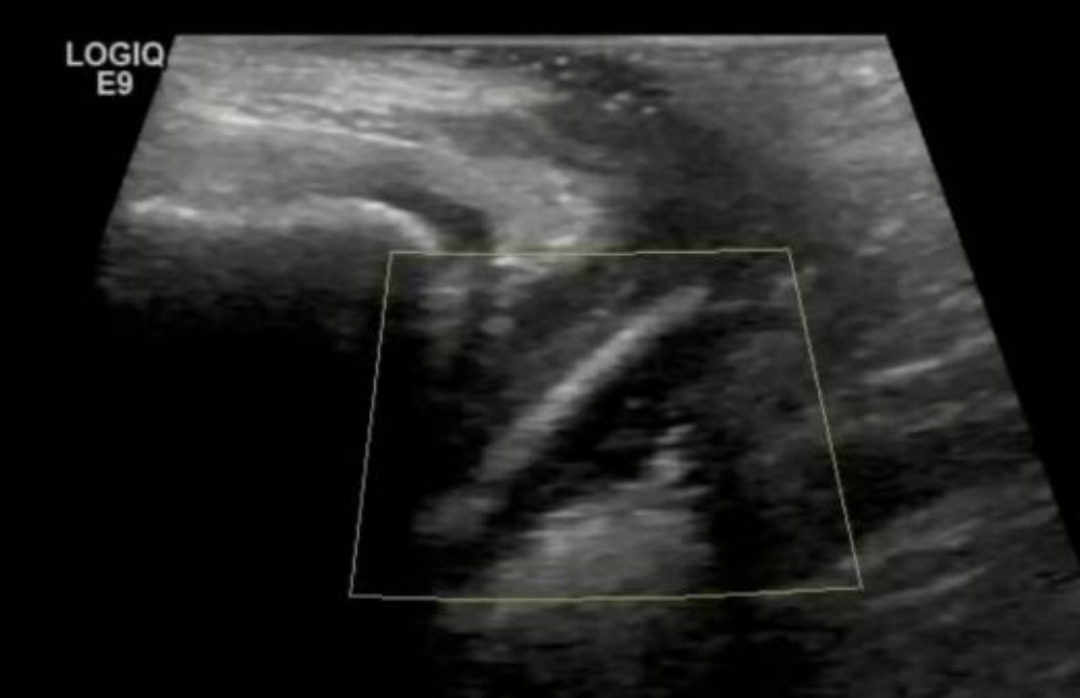

考虑到孩子年龄小,生殖道娇嫩,传统操作极易造成损伤,妇六区张蕾主任医师决定为小女孩实施阴道内镜检查+异物取出术。

用内镜看清楚阴道内情况的那一刻,在场医护都惊呆了:孩子阴道内竟然卡着一支完整的试用装精华液!

后续手术过程非常顺利,在内镜指引下,医生几分钟就把那支精华液小样完整无损地取出来,未损伤阴道瓣和阴道黏膜,完整保护了儿童生殖器官的完整性与生理功能。